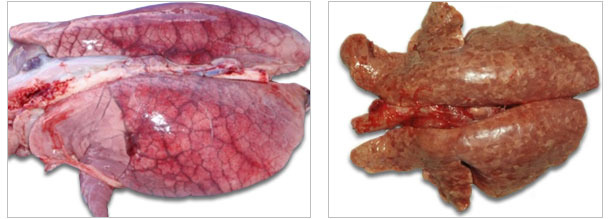

Tinção positiva (castanha) para PCV2 mediante imunohistoquímica no pulmão

de um porco com edema interlobular severo e pneumonia intersticial difusa.

| O sindroma do edema pulmonar agudo pode observar-se en PCVAD agudos. |

Pulmões escuros e endurecidos (padrão intersticial de pneumonia) de um porco com pneumonía associada a PCV2. |